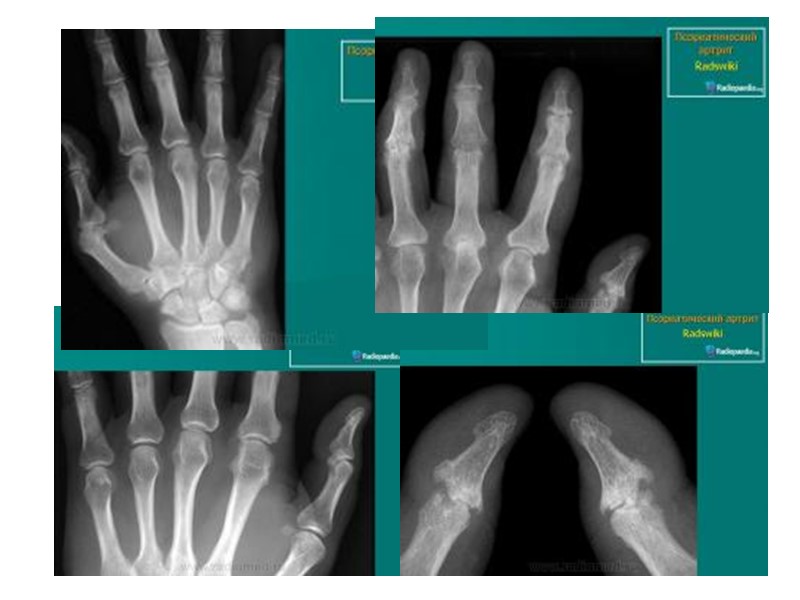

Рентгенологические признаки, помогающие отличить псориатический артрит от других воспалительных ревматических заболеваний суставов: Асимметричность поражения суставов кистей. Артрит на рентгенограммах может быть без околосуставного остеопороза. Изолированное поражение дистальных межфаланговых суставов кистей при отсутствии изменений или небольших изменениях в других мелких суставах кистей. Осевое поражение 3-х суставов одного пальца. Поперечное поражение суставов кистей одного уровня (одностороннее или двухстороннее). Деструкции концевых фаланг (акроостеолиз). Концевое сужение (атрофия) дистальных эпифизов фаланг пальцев рук и пястных костей.

Рентгенологические признаки, помогающие отличить псориатический артрит от других воспалительных ревматических заболеваний суставов (продолжение): Чашеобразная деформация проксимальной части фаланг пальцев кистей вместе с концевым сужением дистальных эпифизов - симптом «карандаш в колпачке» . Костные анкилозы, особенно проксимальных и дистальных межфаланговых суставов кистей. Множественный внутрисуставной остеолиз и деструкции эпифизов костей с разнонаправленными деформациями суставов (мутилирующий артрит). Воспалительные изменения в крестцово-подвздошных суставах -сакроилеиты (обычно двухсторонние асимметричные или односторонние; возможно отсутствие сакроилеита). Изменения в позвоночнике (асимметричные синдесмофиты; паравертебральный оссификат) .

Новая кость сужение суставной щели эрозии Веретенообразная припухлость мягких тканей